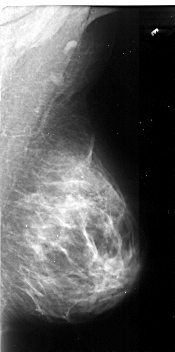

A_1105_1.LEFT_MLO

LEFT_MLO LINES 5296 PIXELS_PER_LINE 3061 BITS_PER_PIXEL 16 RESOLUTION 42 OVERLAY